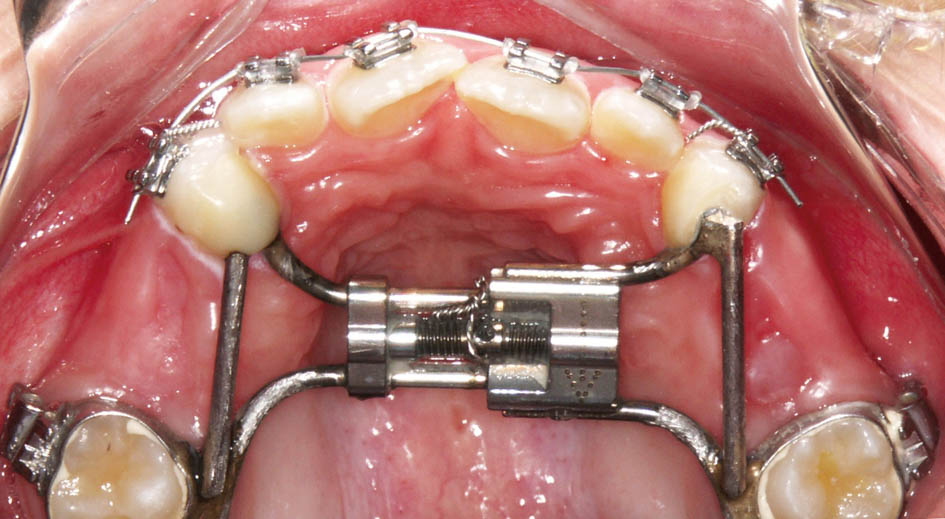

همانطور که ذکر گردید برای کراس خلفی یک پیچ RPE (شکل 41-5) بههمراه اسپیلینت پائین و برای کراس قدامی دندانها، چند براکت و یک اسپیلینت آکریلی پائین بسازید (اسپیلینت آکریلی پائین در هر دو درمان فوق مشترک است).

شکل 41-5: ساخت RPE برای درمان کراس بایت خلفی و چسباندن چند براکت برای پروترود کردن قدامیها جهت درمان کراس بایت قدامی، البته در فک پائین باید یک اسپیلینت متحرک آکریلی داشته باشد.